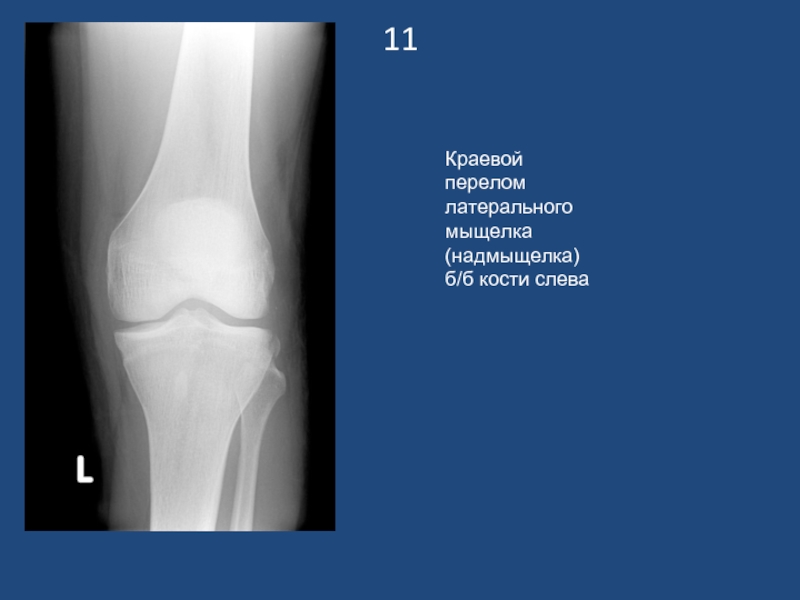

Слайд 1211

Краевой перелом латерального мыщелка (надмыщелка) б/б кости слева